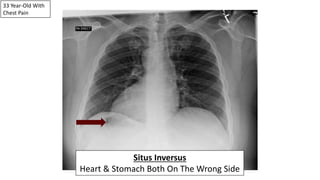

33 Year-Old With

Chest Pain

Situs Inversus

Heart & Stomach Both On The Wrong Side